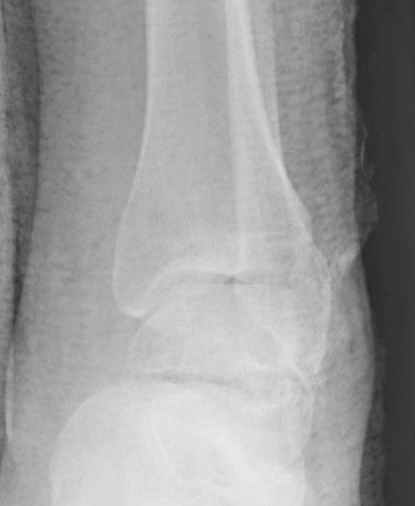

Вдогонку по поводу перелома таранной кости, больная 81, не страдает диабетом, перелом закрытый, в первый же день поступления ограничились временным наружным фиксатором (как на снимке).

Планировалась открытая фиксация после спадения отека, но больная пожелала лечиться по месту жительству в другом штате..

За пару недель насчитал 5 больных с переломом таранной кости, из них двое с двусторонним повреждением.

Из-за отека на стопе тактика лечения у всех была

одинаковая: временная наружная фиксация до спадения отека, при изолированных переломах они выписывались домой и через дней 7 госпитализировались на оперативное лечение.

Примеры на снимке...